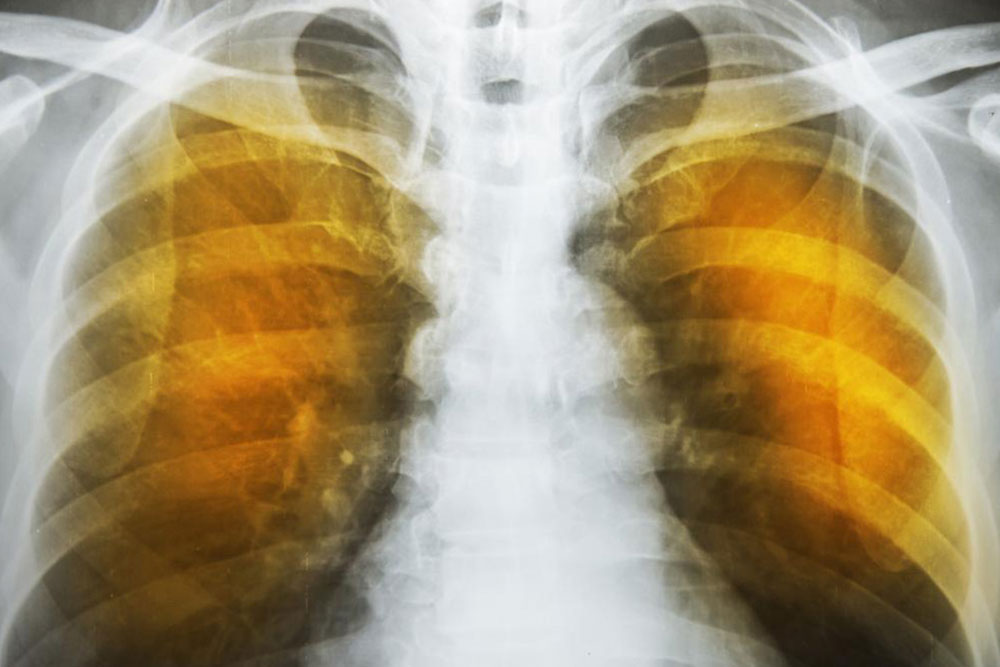

The symptoms of emphysema are exceedingly severe and cause considerable damage to the lungs before the symptoms even show up. Generally, one feels a lack of energy and the tendency to skip some of the common daily routines. It progresses from slight difficulty in breathing to wheezing and then to a persistent cough that does not go away. One starts to feel a tightness in the chest and feels short of breath on exertion. Tiredness and persistent cough become constant.

As the deterioration continues, the alveoli lose their strength and start rupturing. In extreme cases, there may be large scale destruction which leads to empty spaces in lungs called bullae. This would reduce the functional area of the lung which in extreme cases call for surgical removal. In an extremely rare condition, large scale rupture of alveoli can cause a condition called pneumothorax and the collapse of the lung, a very serious condition, which can be fatal. The best thing one can do is stop exposure to irritants.